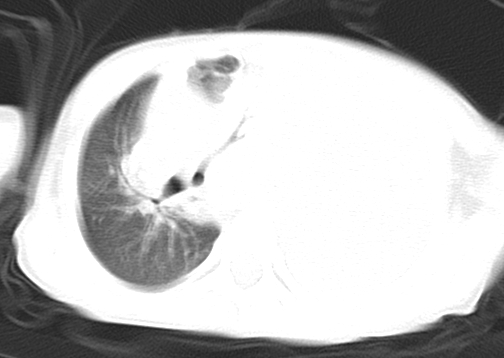

患儿 女 4岁,发热 咳嗽 胸透 考虑:左侧脓胸

左侧胸廓内见大量密实阴影,肺尖部尚有少量肺组织影,纵膈明显受压移位,肋骨未见明显受侵征象,虽然病人年龄较小,但如此大量的“积液”,还是要警惕,不同意一般感染,可结合穿刺脱落细胞学检查。

1)考虑左肺炎症感染。2)左侧大量胸腔积液。

1)考虑左肺炎症感染。2)未经穿刺只能定左侧大量胸腔积液。

左侧张力性大量胸腔积液压迫性肺不张、感染;建议治疗后复查。